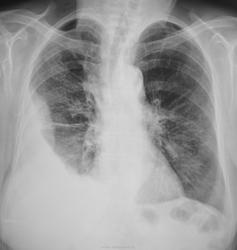

Пациентка направлена на рентгенографию ОГК с диагнозом пневмония.

Снимки произведены в выходной день. Какие мнения будут уважаемые коллеги?

Правосторонний гидроторакс. К хирургу, потом на контроль.

помимо гидроторакса мне видятся очаговые тени в верних отделах легких,томографию надо

Правосторонняя пневмония осложнённая плевритом.